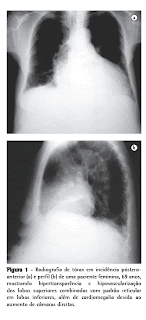

TÓRAX COM EDEMA PULMONAR

Tórax com edema pulmonar indica a presença de acúmulo anormal de líquido nos pulmões, uma condição séria que exige atendimento médico de emergência. No tórax, isso se manifesta como dificuldade para respirar, tosse (possivelmente com espuma ou sangue), chiado e sensação de sufocamento.